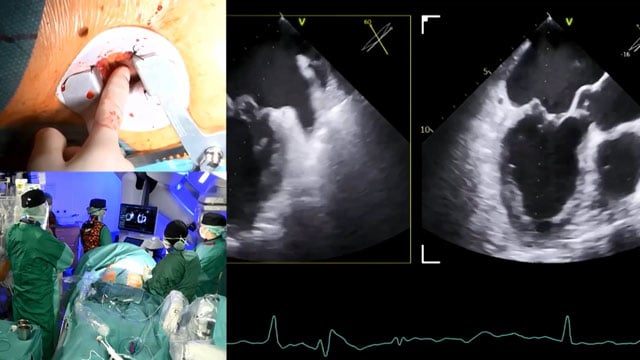

Mitral TEER and LAA closure: LIVE Educational Case from Clinique Pasteur - Toulouse, France

This educational session presents a live case from Clinique Pasteur, Toulouse, France, focusing on Mitral Transcatheter Edge-to-Edge Repair (TEER) combined with Left Atrial Appendage (LAA) closure. Attendees gain insights into patient evaluation, operator strategies, device selection, and procedural execution, complemented by a recorded case from Upper...

Complex valve-in-valve leaflet modification: LIVE Educational Case from Clinique Pasteur - Toulouse, France

Delve into a complex valve-in-valve leaflet modification through a LIVE educational case from Clinique Pasteur, Toulouse, complemented by expert analysis and a recorded case from Erasmus University Medical Center, Rotterdam. This session presents patient imaging, operator strategy, and detailed procedural insights that enhance understanding of advanced...

Mitral TEER: LIVE Educational Case from Hospital Álvaro Cunqueiro - Vigo, Spain

This live educational case from Hospital Álvaro Cunqueiro in Vigo, Spain, offers an in-depth look at Mitral TEER, including patient presentation, imaging analysis, operator strategy, and device overview. The session also features a recorded case from the Heart and Diabetes Center NRW in Germany, providing comprehensive...